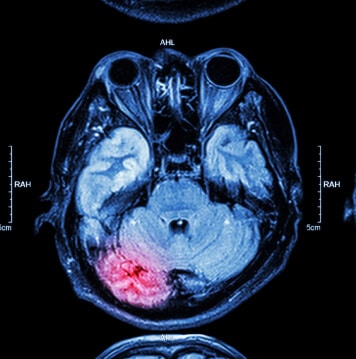

Estas conclusiones se obtuvieron después de que los investigadores examinaran los resultados de imágenes cerebrales capturadas mediante resonancia magnética y tecnología de imágenes por tensor de difusión.

El equipo también descubrió que el daño cerebral causado por un traumatismo craneoencefálico puede ser a largo plazo, si no permanente. Esto se determinó mediante imágenes cerebrales obtenidas un año después de la evaluación inicial del paciente.